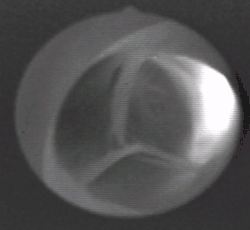

Аорта́льный кла́пан (лат. valva aortae) — один из клапанов сердца человека, или других теплокровных животных, располагающийся на границе левого желудочка и аорты, препятствуя обратному току крови из аорты в левый желудочек в диастолу. У человека клапан имеет три створки, открывающихся в сторону аорты. Полулунные створки, смыкаясь, перекрывают отверстие, соединяющее аорту и левый желудочек. Створки крепятся к фиброзному кольцу, которое образует отверстие между аортой и левым желудочком.

- пик открытия створок, приходится на первую фазу максимального изгнания крови: свободные края створок максимально изгибались в сторону синусов, форма открытия клапана приближается к кругу;

- период устойчивого открытия створок, приходится на вторую фазу максимального изгнания крови: свободные края створок выпрямляются вдоль оси потока, клапан принимает форму цилиндра, и створки постепенно прикрываются, форма открытия клапана становится треугольной;